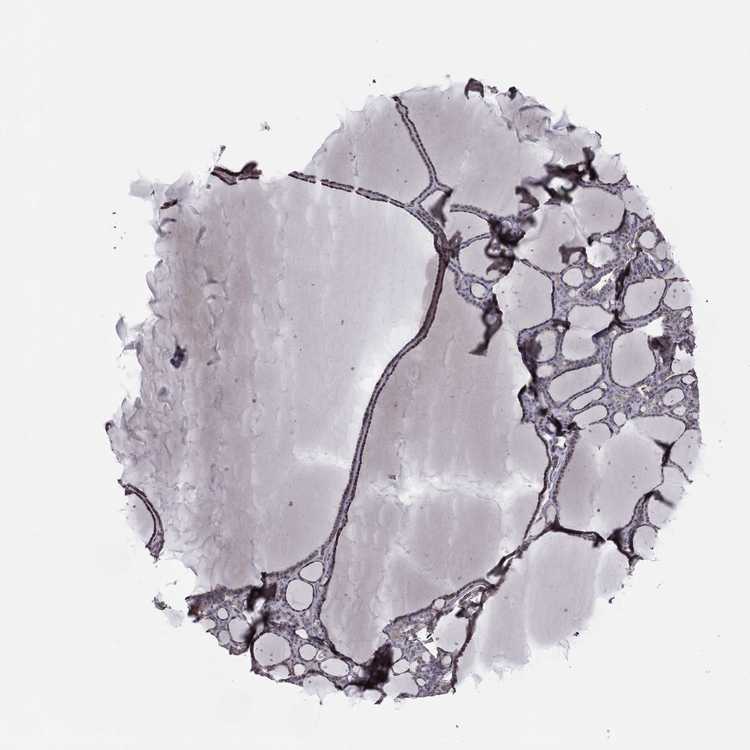

THYROID GLAND - Antibody stainingi

Antibody staining in the annotated cell types in the current human tissue is reported as not detected, low, medium, or high, based on conventional immunohistochemistry profiling in selected tissues. This score is based on the combination of the staining intensity and fraction of stained cells.

Each image is clickable and will lead to virtual microscopy that enables deeper exploration of all samples and also displays staining intensity scores, fraction scores and subcellular localization as well as patient and tissue information for each sample.

Antibody HPA044620Antibody HPA058621

Glandular cells MediumLow